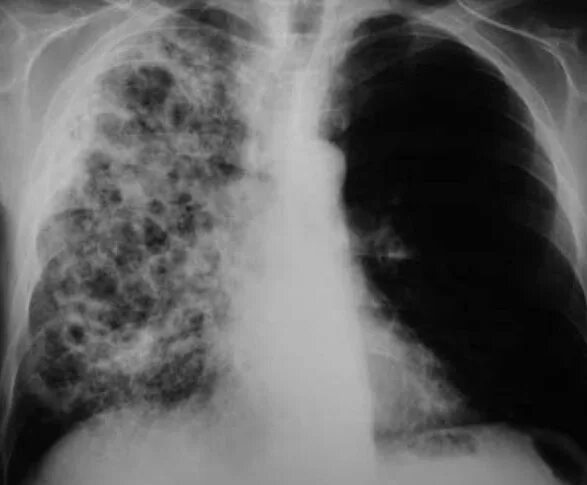

Гистоплазмоз это